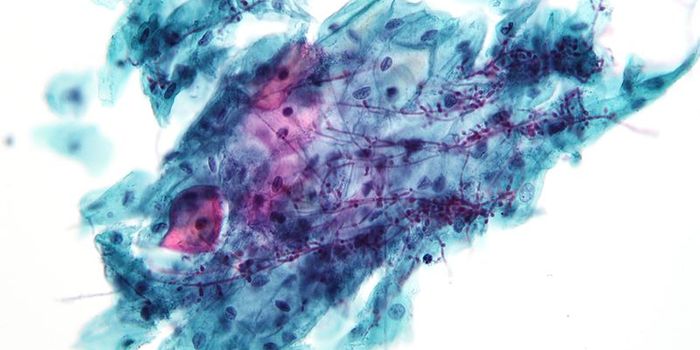

OCT 19, 2023CancerA Pap smear, also called a Pap test or a Papanicolaou test, describes a procedure that removes cells from the surface of ...